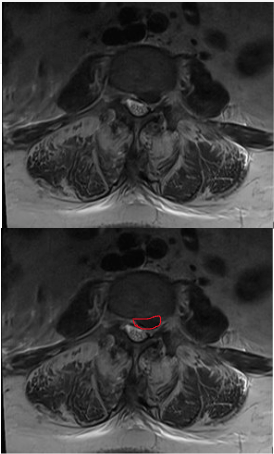

MRI showing a lumbar disk herniation, outlined in red on the bottom.